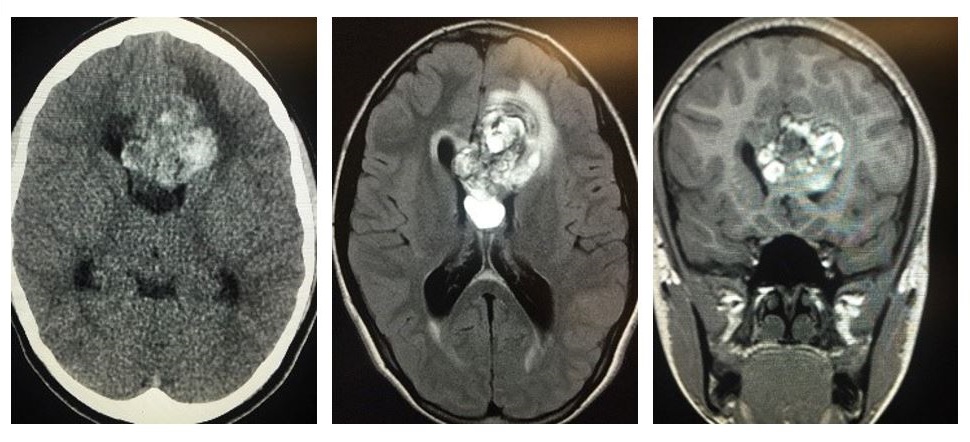

Cerebral cavernous malformations (CCM) is a rare disease that causes anomalies in tiny capillaries that transport blood throughout the brain. The disease manifests as irregularities that resemble raspberries, most often in the brain, that can lead to hemorrhage, stroke and seizures in afflicted individuals. The disease involves defects in one of three CCM genes (CCM1, CCM2, or CCM3) and affects nearly one in six thousand people. Currently, there is no clinically approved therapy to treat this disease; patients rely on invasive brain surgery for treatment, but some extreme forms cannot be treated surgically.

Three brain scans side by side.

CCM irregularities in MRI scans of the brain.